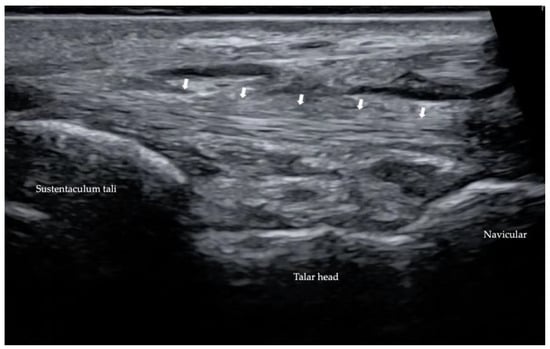

2.3. Ultrasound (US)